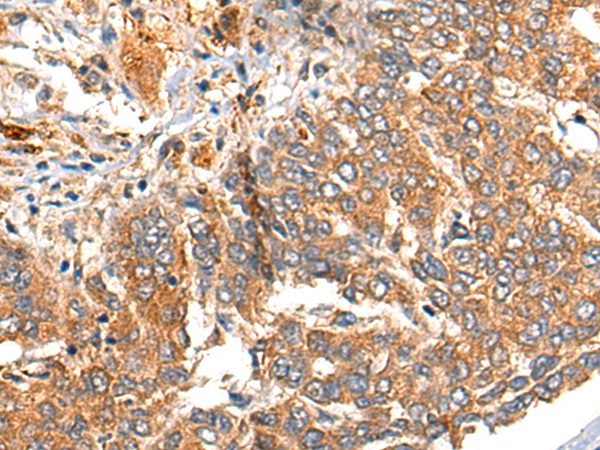

The image on the left is immunohistochemistry of paraffin-embedded Human liver cancer tissue using 46607(MARK2 Antibody) at dilution 1/35, on the right is treated with synthetic peptide. (Original magnification: x200)